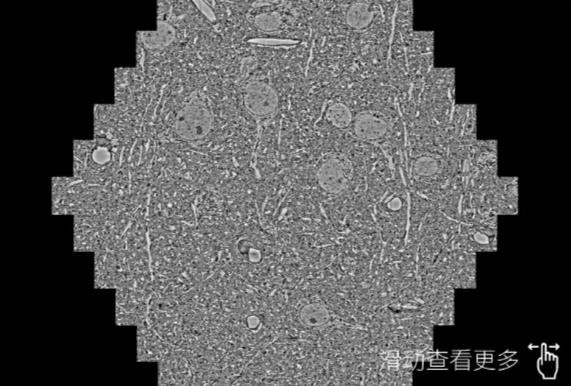

鼠脑切片。左图使用东莞蔡司东莞扫描电镜MultiSEM706对165μmx143pm面积区域成像,耗时仅需1.5秒。右图为鼠脑切片中30μm区域放大效果。样品由芝加哥大学B.Kasthuri提供。